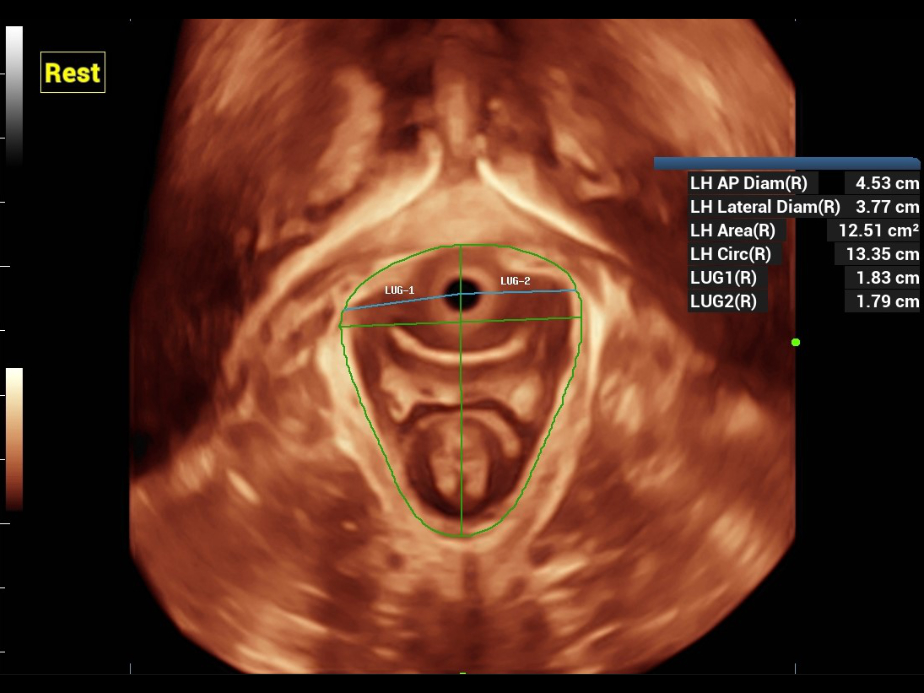

Nuewa provides automatic 2D measurements for the pelvic compartment and an intelligent volume evaluation system, including automated evaluation for levator hiatus and multi-section analysis with automatic measurements.